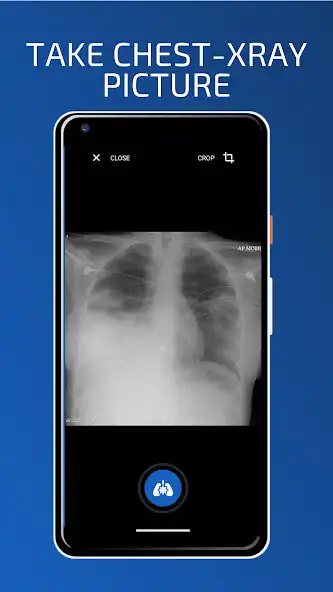

With Artificial intelligence technology we have been able to push the boundaries of medical diagnosis . and help doctors and radiologist perform chest x ray classification faster and more accurate than ever before.

we trained our AI model over 18 most common pathologies : (Atelectasis , Consolidation , Infiltration , Pneumothorax , Edema , Emphysema , Fibrosis , Effusion , Pneumonia , Pleural Thickening , Cardiomegaly , Nodule , Mass , Hernia , Lung Lesion , Fracture , Lung Opacity , Enlarged Cardiomediastinum ) .

With 90% prediction accuracy Neuron offre a very powerful medical diagnosis tool for doctors , and with medical community help we could provide more pathologies and improve diagnosis precision for the benefits of all .